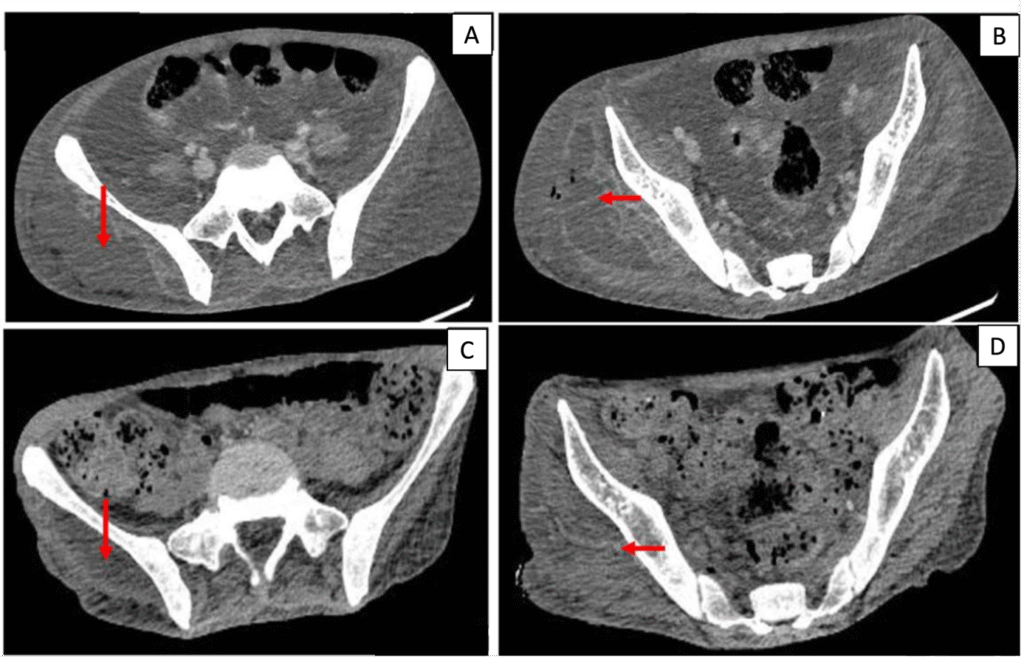

Blood investigations showed a hemoglobin of 9.4g/dl and mild leukocytosis with a total leukocyte count of 11.5 x10^9/uL. Renal and hepatic functions were within normal limits. Inflammatory markers were not available. Blood sugar was uncontrolled with an HbA1C of 11.2%. He was started on insulin infusion, which was later converted to a subcutaneous basal bolus regimen and titrated according to blood sugar monitoring. 2 sets of blood cultures were sent on admission before starting of antibiotics. Contrast-enhanced computer tomography (CECT) of the abdomen and lower limbs showed a multiloculated fluid collection in the subcutaneous plane and inter-muscular plane of the gluteus and quadriceps muscles with erosions in the femoral head and acetabular, suggestive of pyomyositis, although there was no evidence of osteomyelitis. (Figure 1).

Figure 1. Contrast-enhanced CT (CECT) axial images at presentation (A, B) and during follow-up after treatment (C, D). (A, B) Multiloculated hypodense collections in the subcutaneous and intermuscular planes of the right gluteal and proximal thigh musculature (arrows), consistent with pyomyositis, with adjacent soft-tissue inflammation. (C, D) Interval reduction in the size and extent of the collections following surgical drainage and targeted antimicrobial therapy.